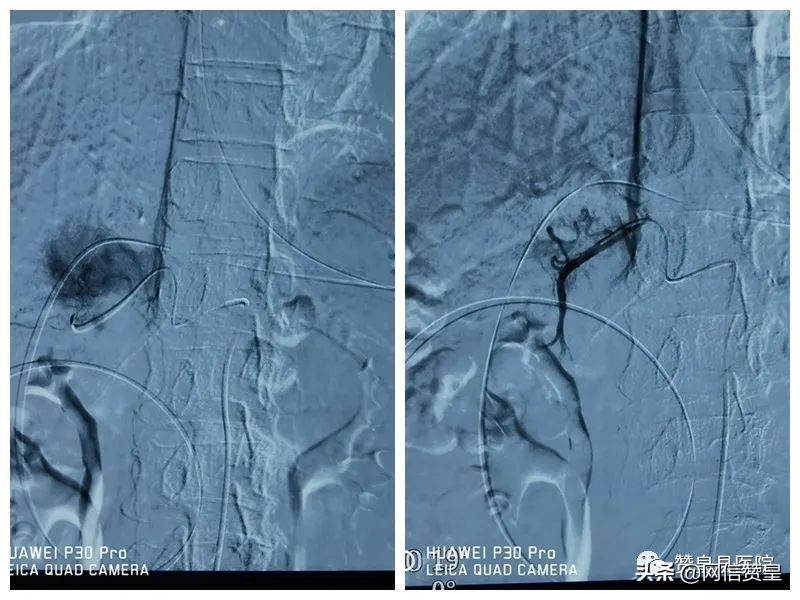

造影肿瘤显示清晰,供血丰富。

术后造影造影显示栓塞良好。